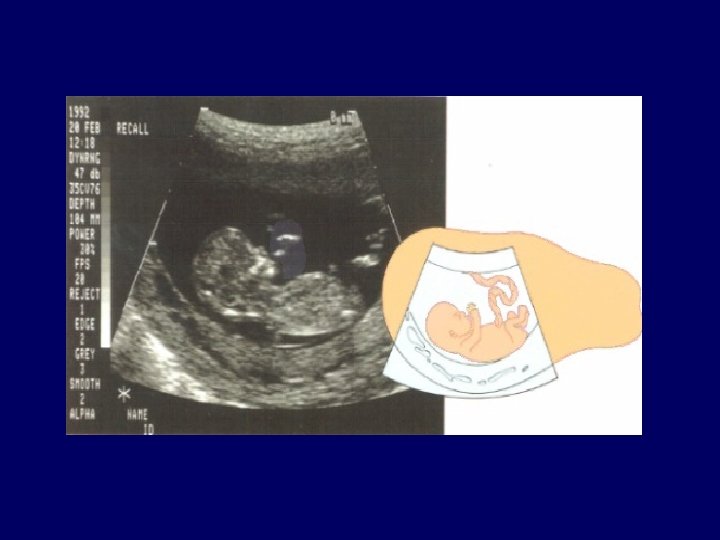

Investigation • Age ﺍﻳﺸﺎﻻ ﻣﻮﺑﺎﺭﺍﻙ ﺑﺎﺩﺍ • Family history, AFP • Ultrasound • Invasive testing : CVS • Follow-up